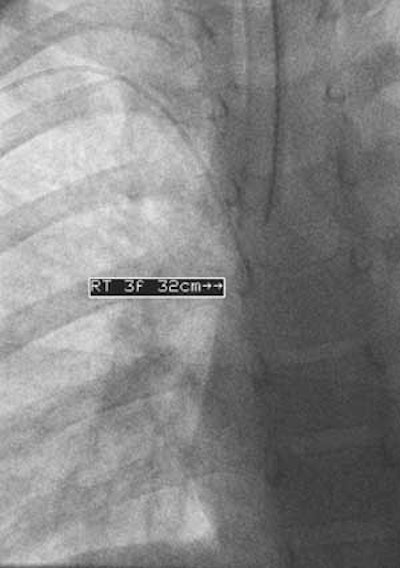

| Dr. John Racadio placed a 0.014-inch hydrophilic guidewire through the catheter and maneuvered through the tortuosity into the superior vena cava, as shown in the final placement image here. "You can imagine how this PICC placement would have been impossible if the attempt were at the bedside without fluoro assistance," noted Racadio. |